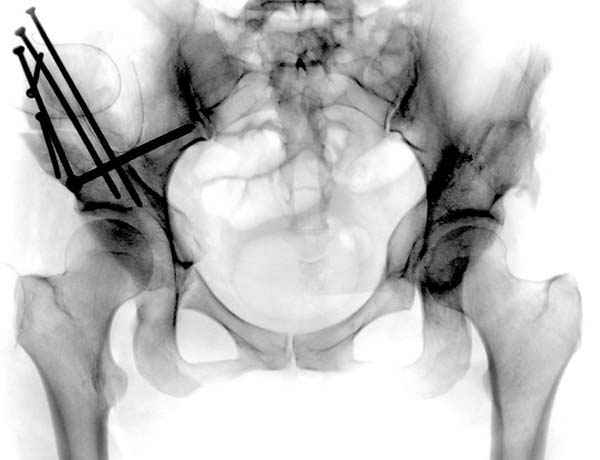

Но, занимаясь с этой патологией, собрал небольшой опыт в лечении остеоартрита, включая: периацетабулярную (ориентационно-корригирующую) остеотомию, и на проксимальной части бедра - valgus, varus, flexion and extension osteotomy и в комбинациях, базирующуюся на авангардных учениях Reinhold Ganz из Bern, на конгруентности сустава и увеличения контактной площади в суставе для уменьшения давления на площади хряща, При Вашем желании можно продемонстрировать результаты наших операций на слайдах.

Если Вам не трудно, не смогли бы Вы представить материал о том, в каких из перечисленных 1500 Ваших операций и 1500 ассистенциях, было применено Ваше открытие по коррекции тазобедренного сустава, потому что морфомеханика связана с варус или валгус остеотомиями на проксимальном отделе бедра.

Мною произведены измерения на 290 рентгенограммах ТБС у молодых лиц обоего пола (средний возраст их 26.919 лет) без признаков патологии означенного сустава. Согласно точным расчетам плечо массы тела в среднем составило 107.685 мм (расстояние от центра головки бедренной кости до средней линии тела). Согласно тем же точным расчетам плечо силы реакции связки головки бедра равняется в среднем 35.190 мм (расстояние от центра головки бедренной кости до дна ямки вертлужной впадины, где прикрепляется проксимальный конец связки головки бедра). Соответственно плечо веса тела относится к плечу силы реакции связки головки бедра как 1:3,060, это если быть точным… Я допускаю, что есть проекционные искажения, эффект увеличения изображения на рентгенограмме, погрешности в измерениях, индивидуальная изменчивость размеров, быть может я недостаточное количество суставов обмерил, точку проксимального крепления связки головки бедренной кости на рентгенограмме не видно, а линия действия ОЦМ в одноопорном ортостатическом положении смещается от центра в сторону ТБС на разную величину, обусловленную антропометрическими особенностями и т.д.… именно поэтому в своем сообщении я указал соотношение 1:3, и назвал его приблизительным».

«Авангардное учение Reinhold Ganz из Bern», основанное на улучшении конгруэнтности в ТБС и увеличении контактной площади в суставе для уменьшения давления на хрящ, как раз и доказывают, что ведущей причиной деструкции хряща при коксартроза являются высокие напряжения в верхнем секторе сустава. В норме напряжения здесь существенно меньше, чем в нижнем секторе. Reinhold Ganz из Bern манипулируя с суставными концами, как раз и пытается снизить возникающие при артрозе высокие среднепостоянные напряжения. За счет более толстого хряща и некоторых других компенсаторных механизмов ТБС некоторое время компенсирует всплеск среднепостоянных напряжений, но механика берет свое, хрящ истирается, а когда кость начинает тереться о кость даже большая площадь их контакта не поможет, поговорите с пациентами. Интересно отметить, что при высокой способности организма к компенсации он сам без Ваших остеотомий значительно увеличивает площадь контакта при коксартроза за счет деформаций, углублений вертлужной впадины, ликвидации ямки головки бедра, краевых разрастаний… С большим желанием ознакомлюсь с Вашими результатами операций на слайдах, но еще больше будет интересно посмотреть их результат через несколько лет, и поговорить с пациентами, а потом с тем, кто будет протезировать этот обезображенный сустав.